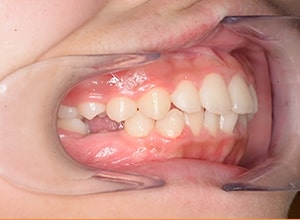

| 口腔内所見 | over jet 3.5mm,over bite4.0mm、下顎正中右側偏位2.0mm、大臼歯関係は左側Ⅰ級であったが、右下6は右下E早期喪失のため近心傾斜しておりⅢ級の臼歯関係となっていた。また上下顎前歯は軽度の叢生を呈していた。 |

| パノラマ所見 | 右下5は右下6近心傾斜により萌出部位不足が認められた。上下顎8歯胚が確認できた。 |

| 批評・予后 | 右下5及び7の萌出前に右下6を整直させることによって、右下5の自然萌出が可能となり正常咬合への咬合誘導が行えたと思う。 |